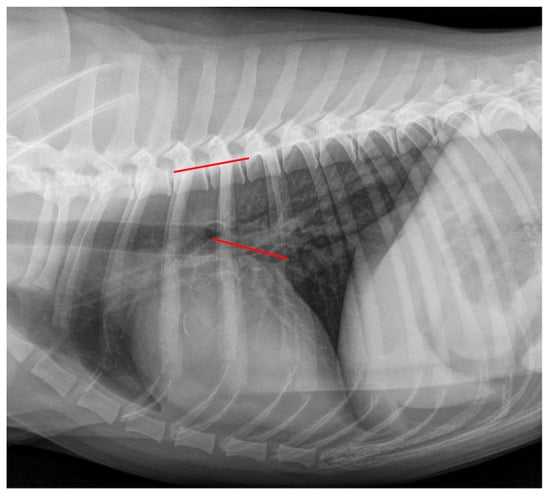

2.4. Radiographic Measurements